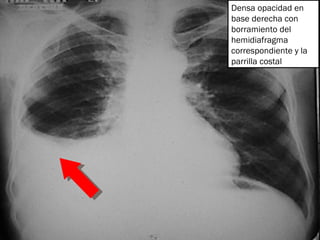

Densa opacidad en base derecha con borramiento del hemidiafragma correspondiente y la parrilla costal

Hemitorax derecho: Derrame pleural Hemitorax Izquierdo: Derrame sub pulmonar